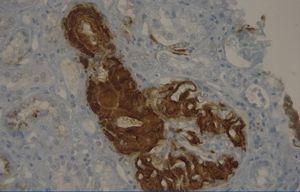

A 29-year-old man of southern Italian ancestry, was admitted to the hospital. Since the first months of life he had experienced characteristic febrile attacks associated with sore throat, myalgias, vomiting and diarrhoea. Later the attacks of fever reduced their frequency but in the last year there was an increased frequency of febrile episodes with proteinuria in nephrotic range. On admission his blood pressure was 150/80mmHg and temperature 36.5°C. Heart sounds were clear with regular sinus rhythm and pulse rate was 88 beats/min. Physical examination showed normal findings and no symptoms suggestive of respiratory, abdominal or urinary infection were apparent. Chest radiography and abdominal ultrasonography scan revealed no abnormalities. Laboratory investigations showed proteinuria 9.17g/day, a raised erythrocyte sedimentation rate, a normal C-reactive protein, a total leukocyte count of 12.500/mm3, serum amyloid 3.67mg/L, serum IgD 233UI/ml (normal range 0-100), creatinine 1.09mg/dl. Immunological tests and other laboratory parameters resulted negative or within normal limits. Kidney biopsy: among 28 glomeruli, 18 showed a weakly eosinophilic amorphous material infiltrating the mesangium (Figure 1 and Figure 2). After positive Congo red staining, the deposits revealed apple-green birefringence under polarized light, consistent with the presence of amyloid. On immunochemistry, the amyloid deposits were negative for antibodies against kappa and lambda chains (Figure 3). Clinical and laboratory findings suggested diagnosis of systemic reactive amyloidosis. The research for MEFV, for Familial Mediterranean Fever (FMF) and TNFRSF1A, for Tumor Necrosis Factor Receptor-Associated Periodic Syndrome (TRAPS) mutations was negative; the research for 2 mevalonate kinase (MVK) mutations was positive in heterozygosis, diagnosing the HIDS. The patient started therapy with Anakinra, Interleukin -1 antagonist.

Figure 1. Kidney biopsy